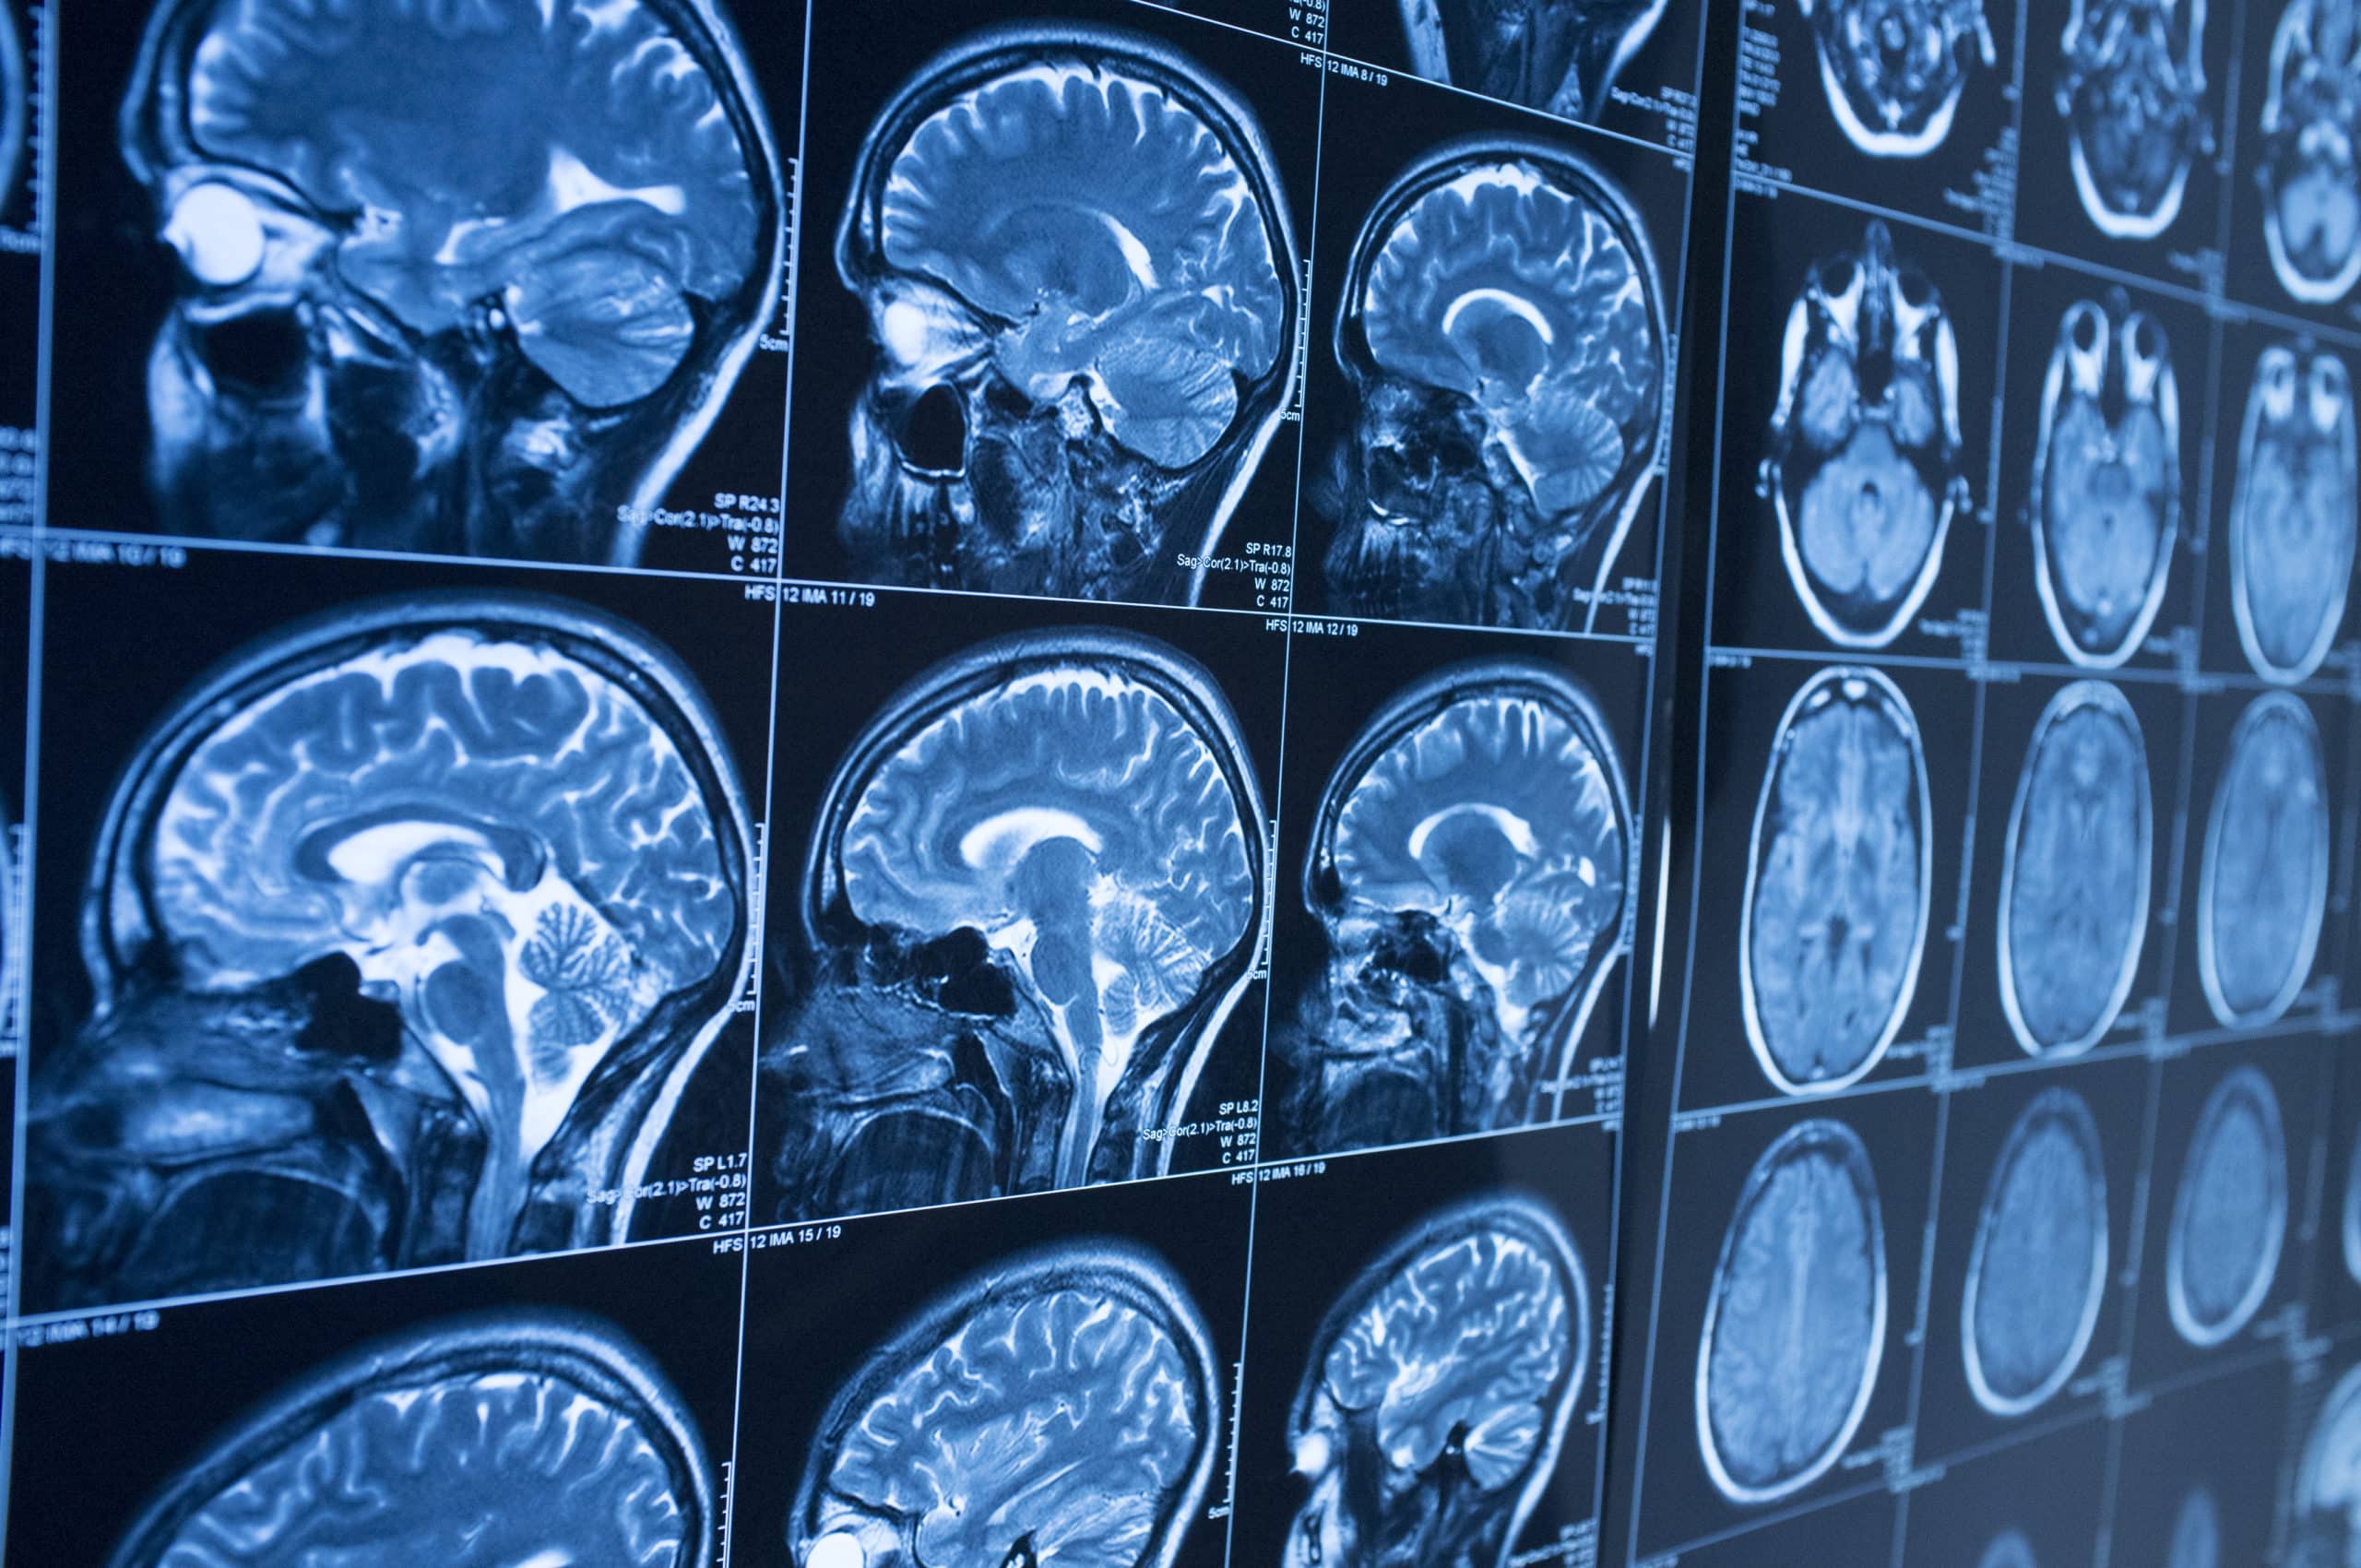

Η απεικόνιση Μαγνητικού Συντονισμού (MRI-Magnetic Resonance Imaging) είναι μια τεχνική, για τη λήψη φωτογραφιών του σώματος χωρίς τη χρήση x-rays ή ακτίνων Χ.

Ο εξοπλισμός, που χρησιμοποιείται, είναι ένας σαρωτής, που παράγει πολύ σαφείς εικόνες υψηλής ποιότητας διαφόρων δομών του σώματος, όπως η καρδιά, ο εγκέφαλος, οι αρθρώσεις και τα εσωτερικά όργανα. Αυτές οι εικόνες, που παράγονται από το συνδυασμό των αποτελεσμάτων των μαγνητικών πεδίων στο υδρογόνο μέσα στο σώμα, μαζί με ένα εξελιγμένο σύστημα ηλεκτρονικών υπολογιστών, στη συνέχεια, προβάλλονται σε μια οθόνη υπολογιστή και μεταφέρονται σε ένα CD και εξετάζονται προσεκτικά από τους γιατρούς.